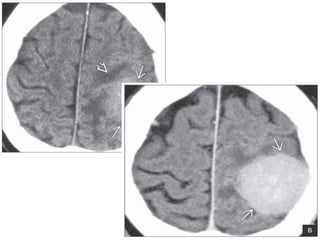

Autopsy (left) and antemortem FLAIR scan (right) in an 8-month-old infant with a supratentorial

PNET shows a large, aggressive-looking hemispheric mass with confluent areas of necrosis and

hemorrhage. There is relatively

little peritumoral edema.Axial T1WI in another infant shows a typical, very large, hypointense

solid, intraaxial mass with distictive lack of peritumoral edema right frontal mass with areas of

necrosis and hemorrhage

Left: axial T2WI MR in the same patient shows a large, mildly

hyperintense right frontal lobe mass. Central &medial tumoral

hyperintensity represents necrosis & heterogeneously hypointense foci

of hemorrhage . Right: axial DWI MR shows restriction diffusion within

this highly cellular mass. Supratentorial PNET.

Autopsy (left) andantemortem FLAIR scan (right) in an 8-month-old infant with a supratentorial PNET shows a large, aggressive-looking hemispheric mass with confluent areas of necrosis and hemorrhage. There is relatively little peritumoral edema.Axial T1WI in another infant shows a typical, very large, hypointense solid, intraaxial mass with distictive lack of peritumoral edema right frontal mass with areas of necrosis and hemorrhage

Left: axial T2WIMR in the same patient shows a large, mildly hyperintense right frontal lobe mass. Central &medial tumoral hyperintensity represents necrosis & heterogeneously hypointense foci of hemorrhage . Right: axial DWI MR shows restriction diffusion within this highly cellular mass. Supratentorial PNET.